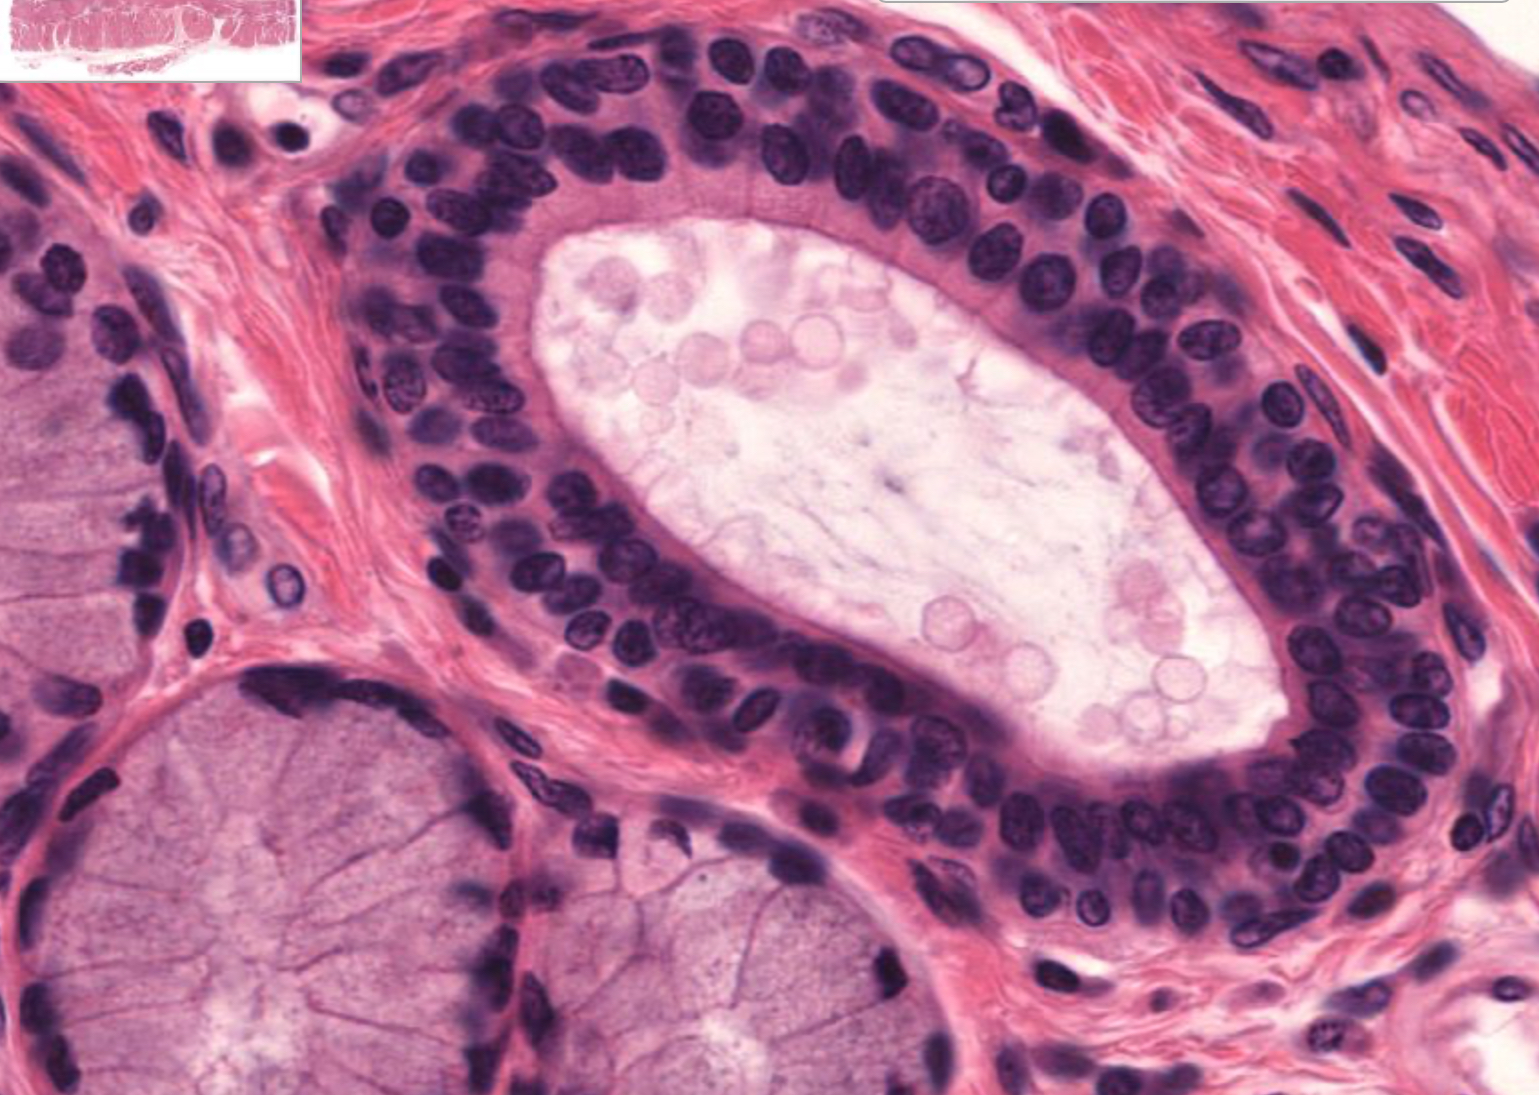

Tissue: transitional epithelium

Location: bladder

also in: ureters, urinary bladder, part of urethra

Function:

• stretches and permits distention